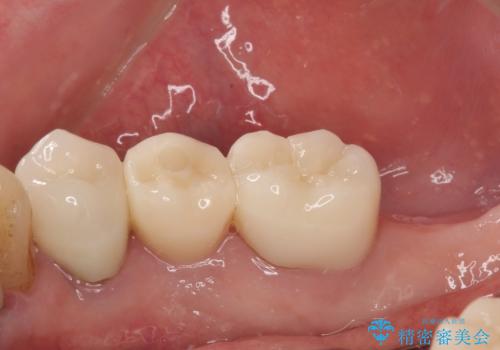

破折してしまった奥歯 抜歯即時埋入で短期間インプラント治療

- 奥歯に装着していたクラウンが外れてしまったとのことで来院された患者様です。

診察したところ、歯根に破折線が確認され抜歯が必要な状態でした。

歯肉や歯槽骨の状態は良好であったため、抜歯即時埋入インプラントによる補綴治療を行うこととしました。

抜歯、インプラント埋入、仮歯の装着を1度に行うことができ、治療終了までわずか3か月で終えることができました。